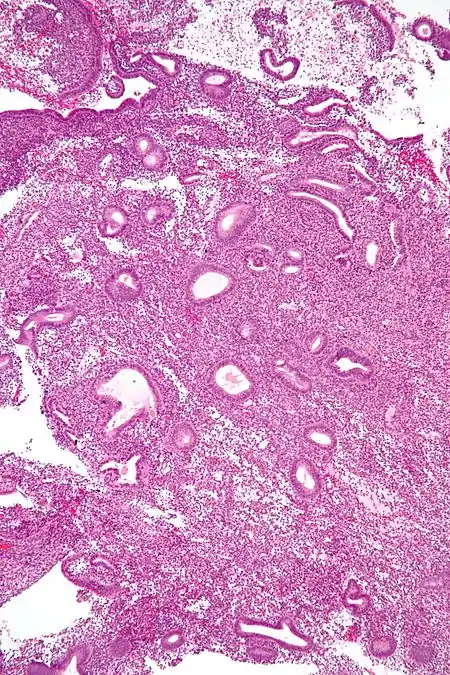

- The tissue will be sent to a laboratory, where it will be processed and tested. It will then be read microscopically by a pathologist who will provide a histologic diagnosis.[4]